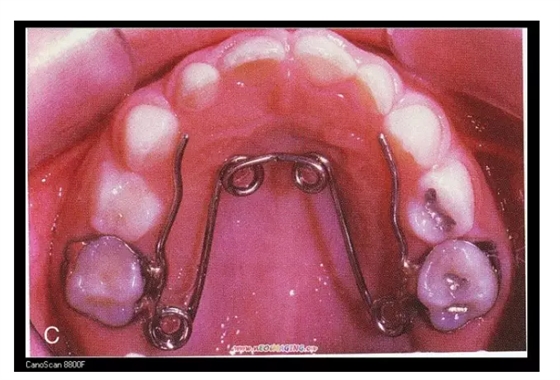

三、擴(kuò)弓器

很多牙列不齊常伴隨牙弓過(guò)窄,所以擴(kuò)弓器是正畸醫(yī)生的好伙伴,它可以以多種形態(tài)和您見面。